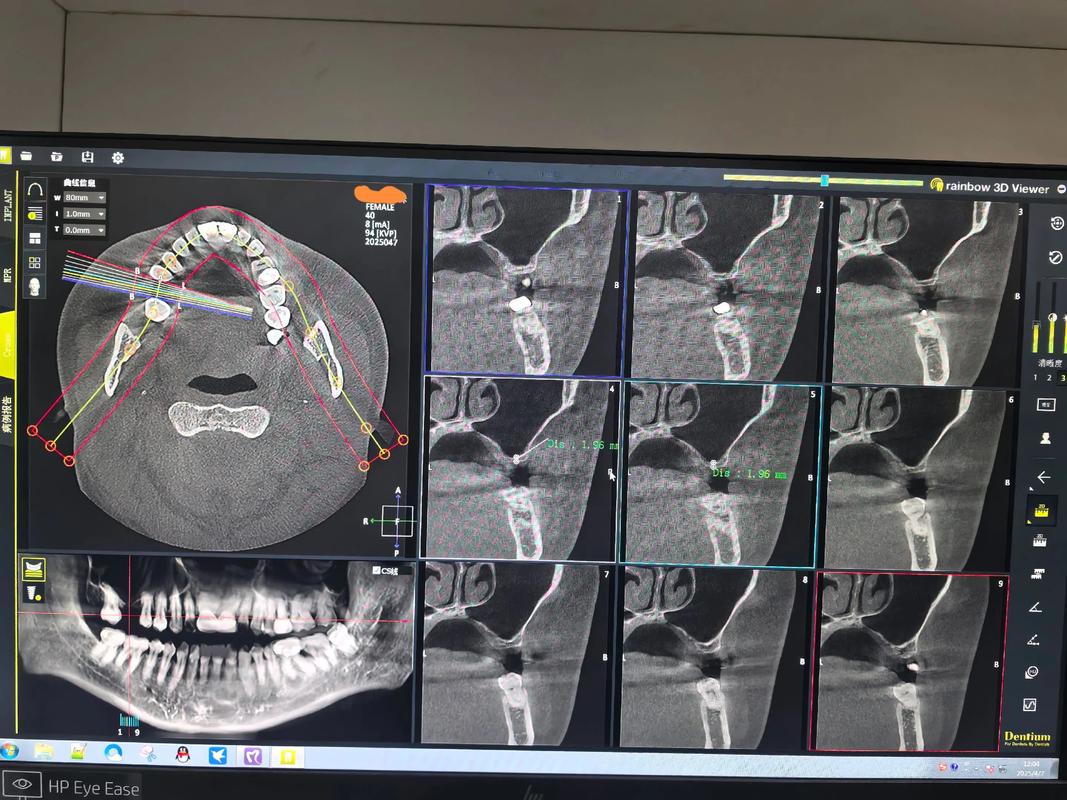

- 影像学检查: 锥形束CT(CBCT)是评估上颌骨骨量的金标准。 它能精确测量牙槽骨的高度、宽度、密度,清晰显示上颌窦的位置、大小、气化程度,以及神经血管管的位置,为制定安全、有效的种植方案提供关键依据。